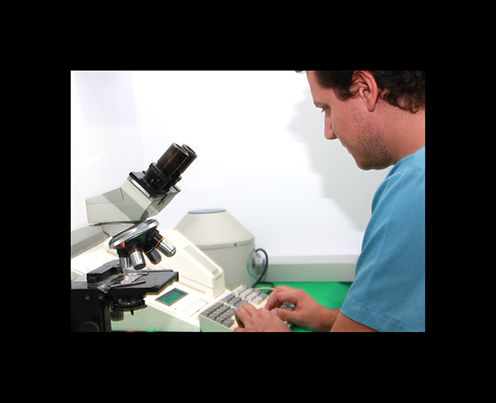

análisis clínicos

En clinican contamos con un laboratorio donde podemos realizar análisis de sangre, orina…